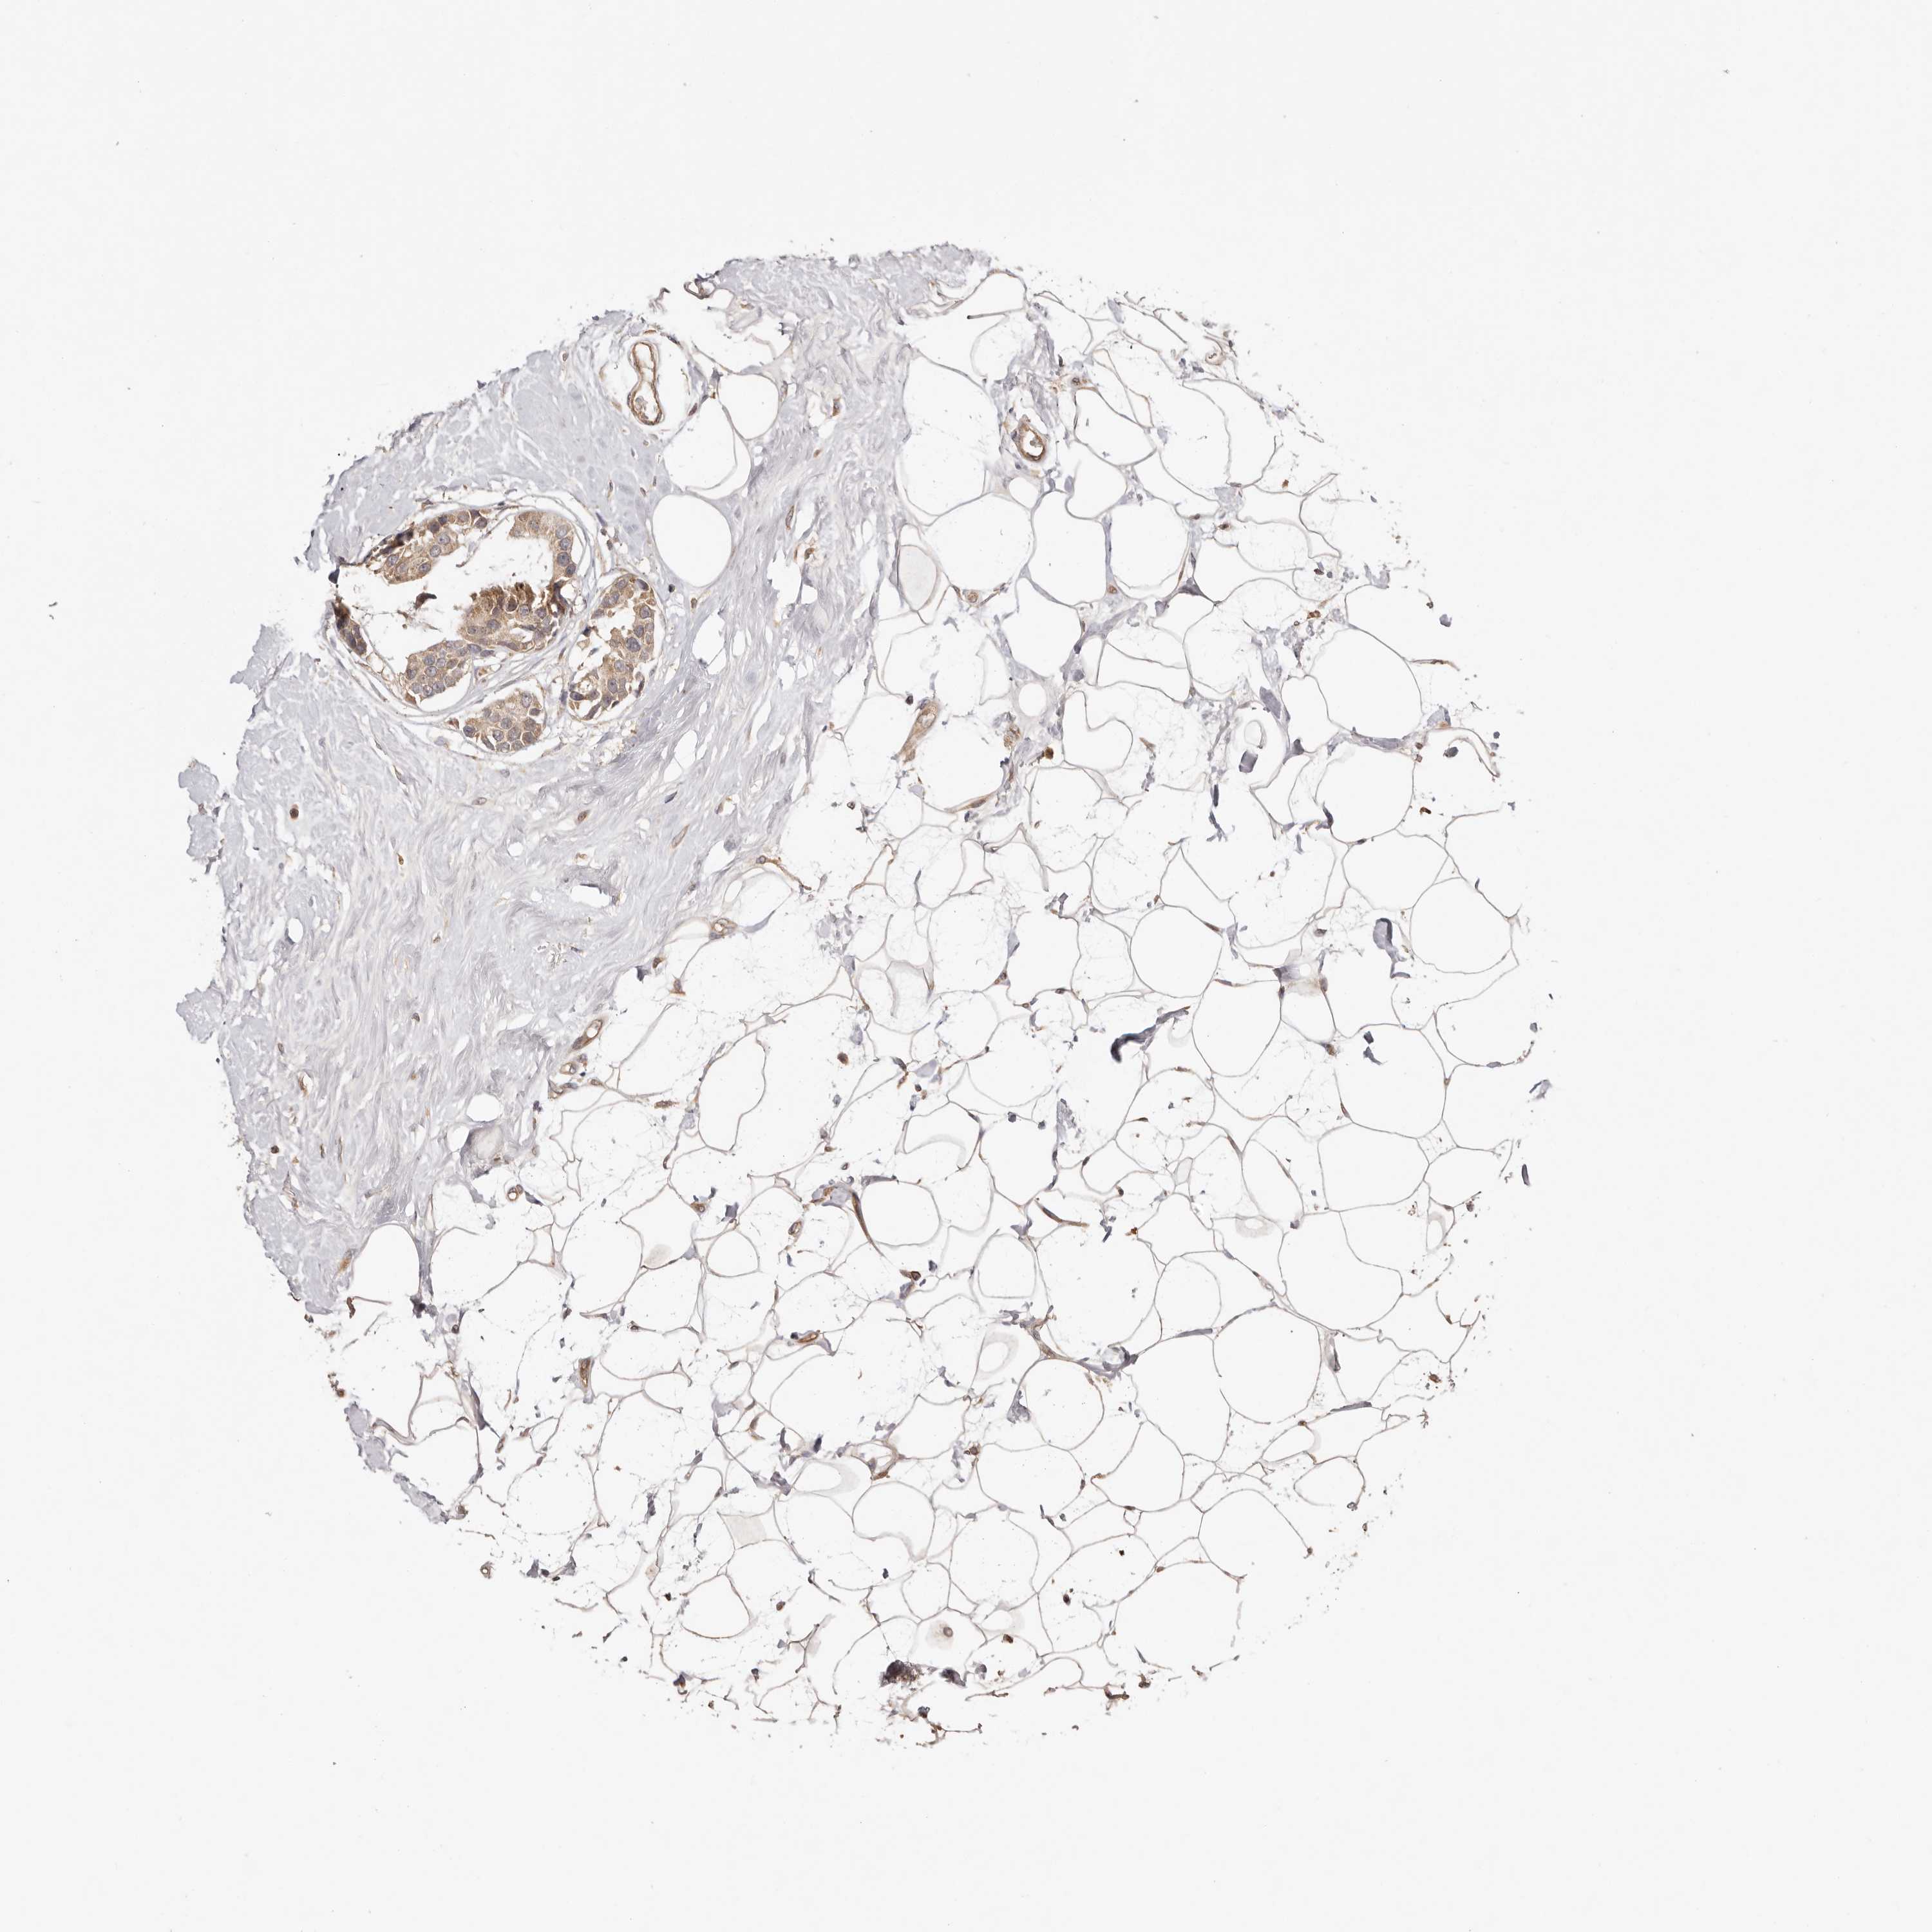

BRCA TCGA BRCA VALIDATION PROTEIN EXPRESSION

Breast cancer

Human cancer